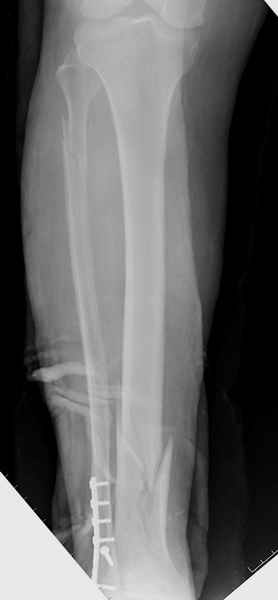

спрашивает что делать с больным который поступил недавно, фермер 55 лет падение при пьяной драке в баре, года два назад перенес операцию на лодыжке, на снимках и КТ перелом без вовлечения сустава,

Повреждение такой локализации, на которой применимы и аппарат (классический Илизарова или гибридный), пластина, особенно Locked Plate, и гвоздь с блокированием. В нашей клинике был бы выполнен закрытый интрамедуллярный остеосинтез. Желательно использовать гвоздь с возможностью провести более чем 2 обычных фронтальных винта в дистальном отломке.

Здесь мы использовали новый Synthes Nail с дополнительными дырками, в проксимальной части 4: по две косых и поперечные (один стандартный а другой динамический), в дистальной части две поперечные, прямая и косая. Вес больного более 120 кг, нагрузку начнем через месяц.

Получилось красиво, поздравляю. Вверху можно было ограничиться одним винтом во фронтальное статическое отверстие, зачем два 45-градусных?

При такий спирали задний край tibia может быть сломан - нет ли этого в данном случае? На всякий случай можно было ввести 1-2 винта 4,5 мм спереди назад мимо гвоздя. Хотя самый дистальный блокирующий винт, возможно, зацепил этот отломок. А какой тут диаметр гвоздя и locking винтов?